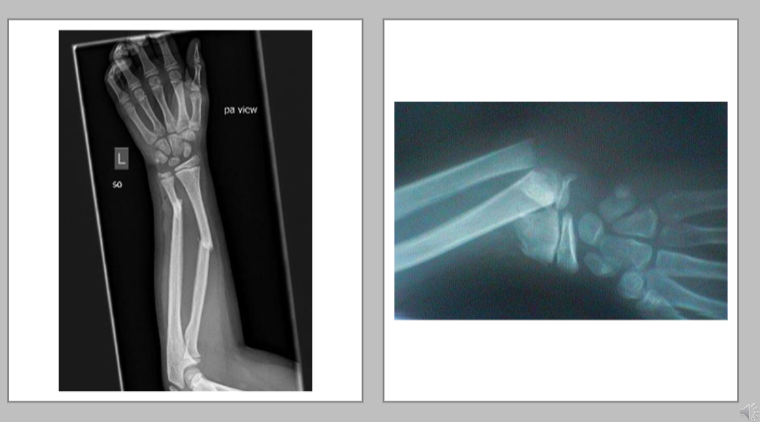

Forearm - Radial/Ulnar

• BBF - both bone fracture usually requires percutaneous pinning

• proximal third radial or ulnar - immobilize elbow

• mid forearm radial/ulnar BBF

• Distal third of forearm (radial ulnar of BBF)

• immobilize the wrist

• align wrist at 0 degrees extension - not functional position

• fracture orthosis with palmar extension (pre-fab)

<ul><li><p>BBF - both bone fracture usually requires percutaneous pinning </p></li><li><p>proximal third radial or ulnar - immobilize elbow&nbsp;</p></li><li><p>mid forearm radial/ulnar BBF&nbsp;</p></li><li><p>Distal third of forearm (radial ulnar of BBF)</p><ul><li><p>immobilize the wrist&nbsp;</p></li><li><p>align wrist at 0 degrees extension - not functional position </p></li><li><p>fracture orthosis with palmar extension (pre-fab)</p></li></ul></li></ul><p></p>

<p>What is unique about this brace?</p>

What is unique about this brace?

It separates the radius from the ulna